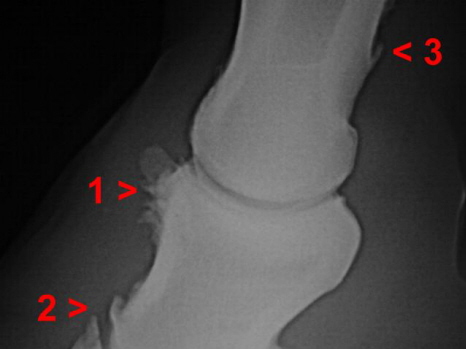

Arthrose Hufgelenk u. Krongelenk